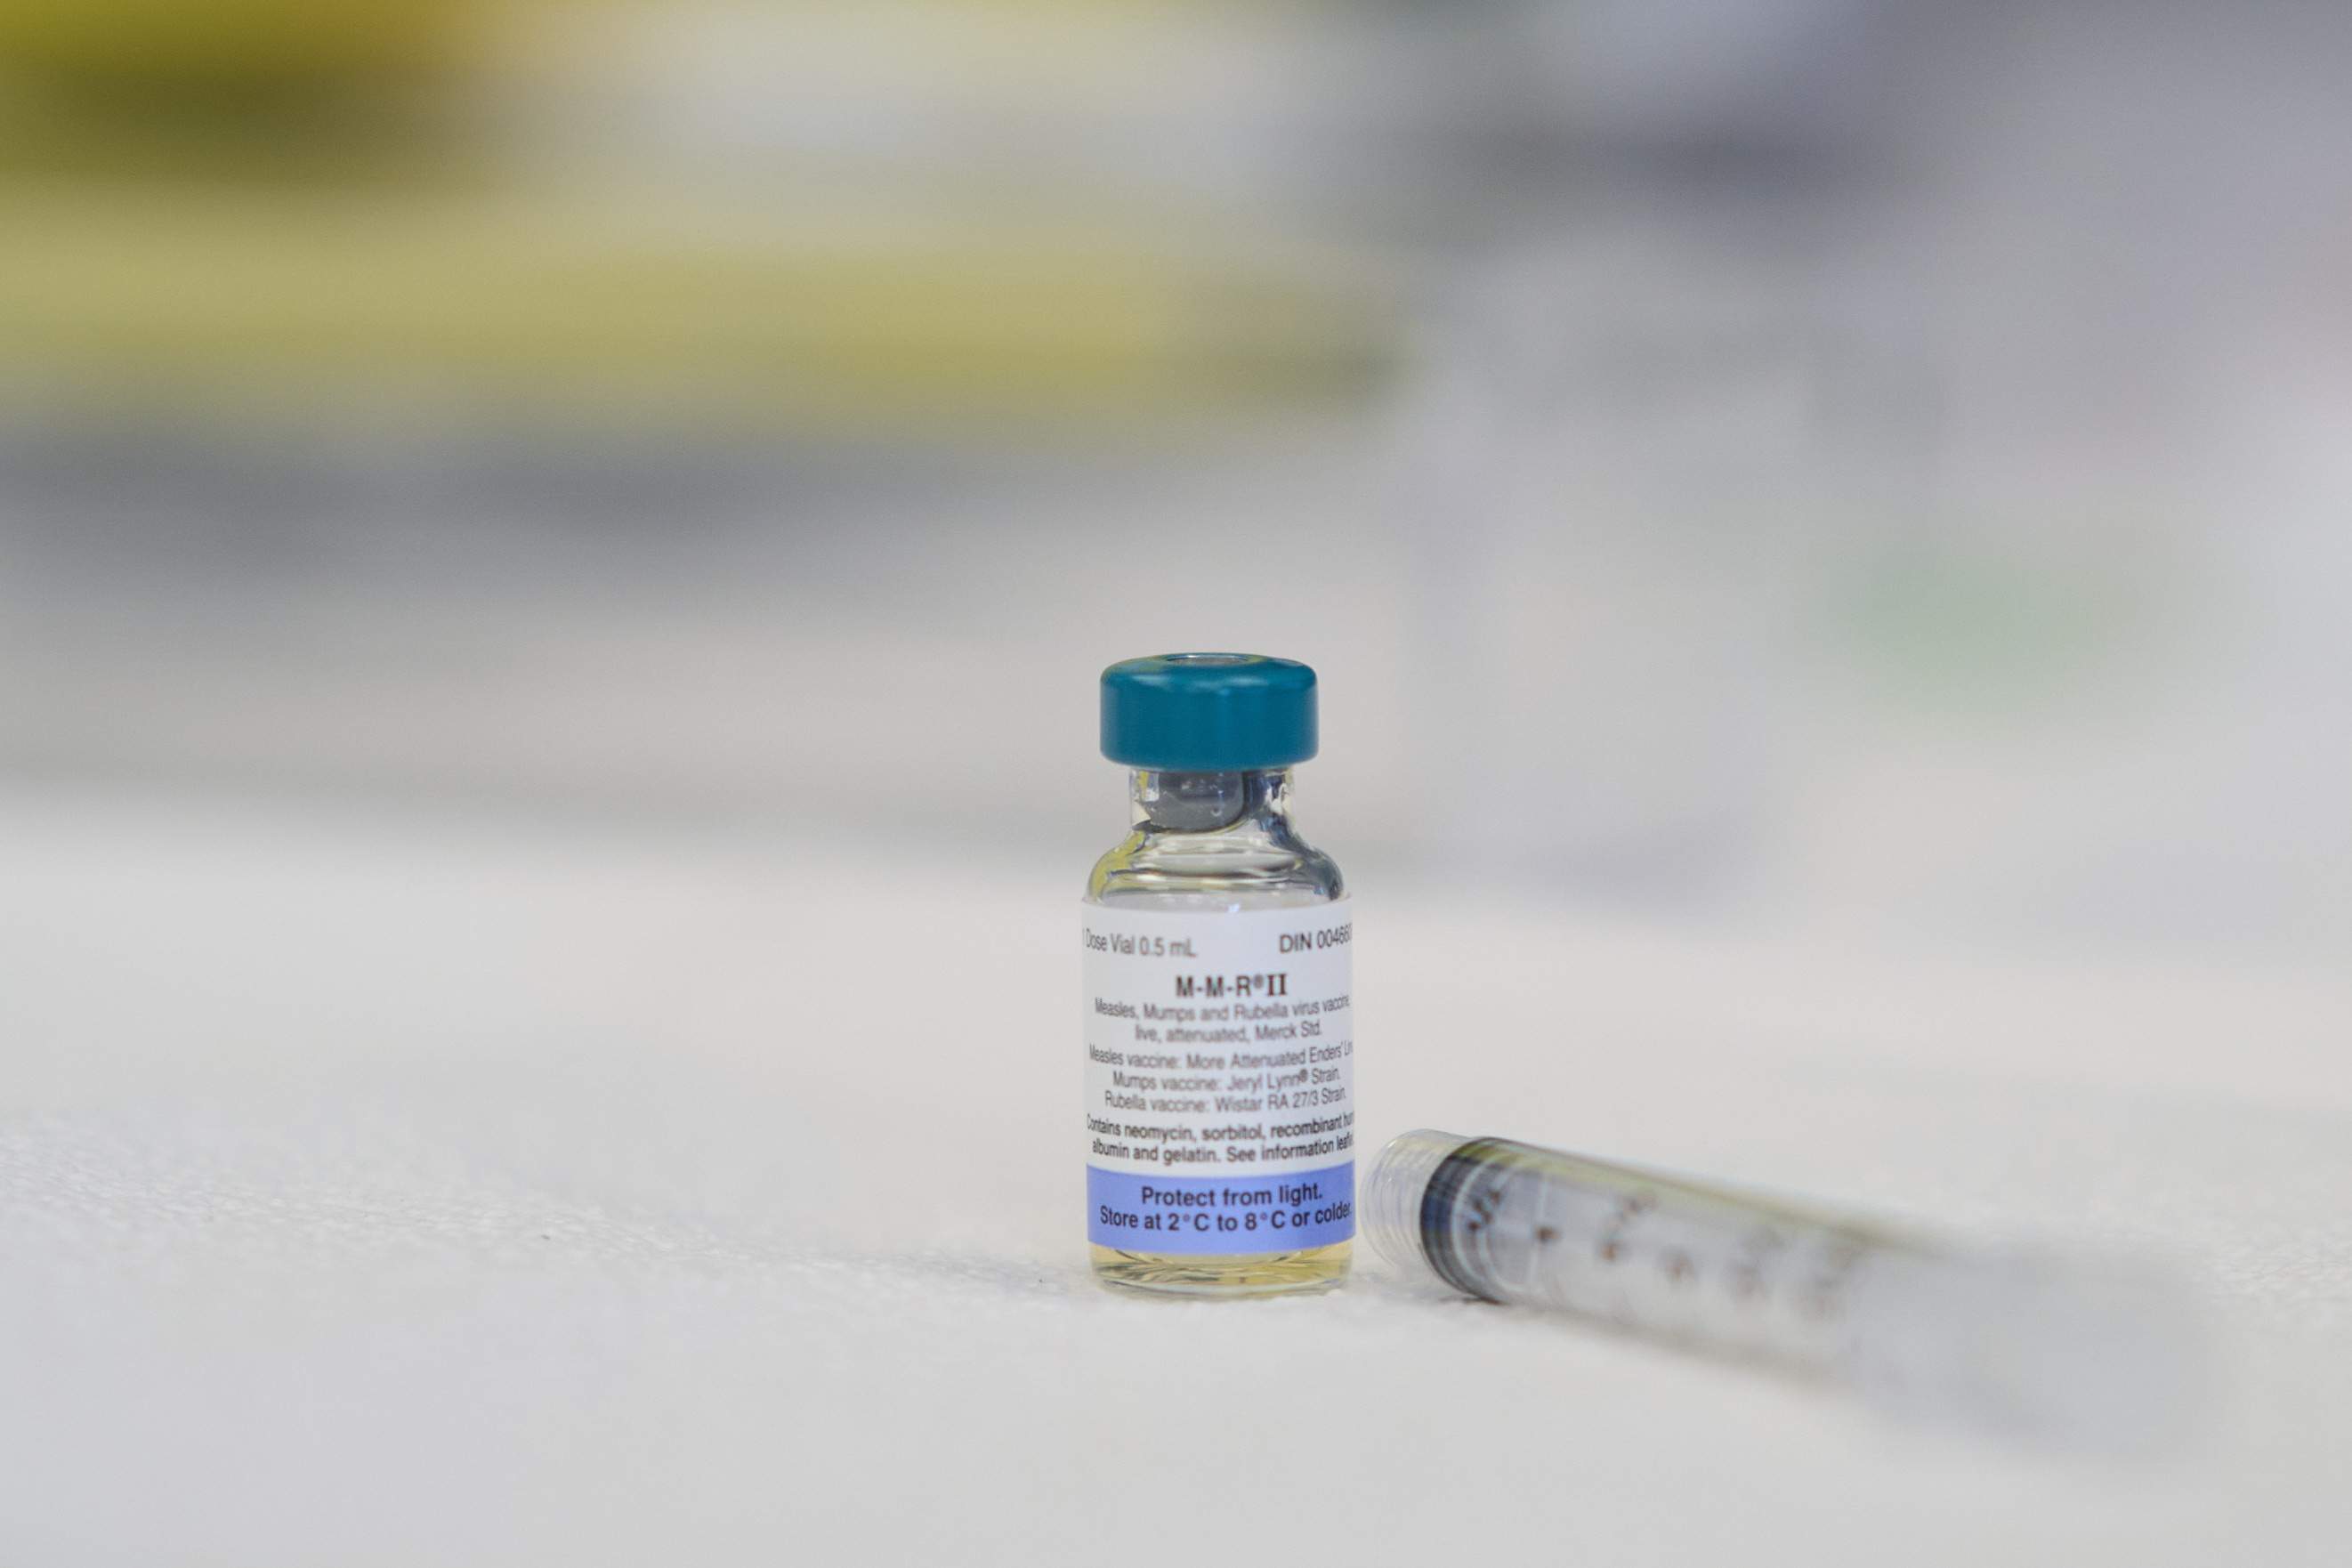

Los casos de sarampión en EE.UU. han superado los 300 desde principio de año, con una niña muerta en Texas sin vacunar

La OMS y Unicef alertan de que el virus en estas regiones está en su nivel más alto en 28 años

En Catalunya se han confirmado una veintena de casos este 2025, más de la mitad que todo el año pasado

Confirmados 25 casos de sarampión en Catalunya hasta el 22 de abril